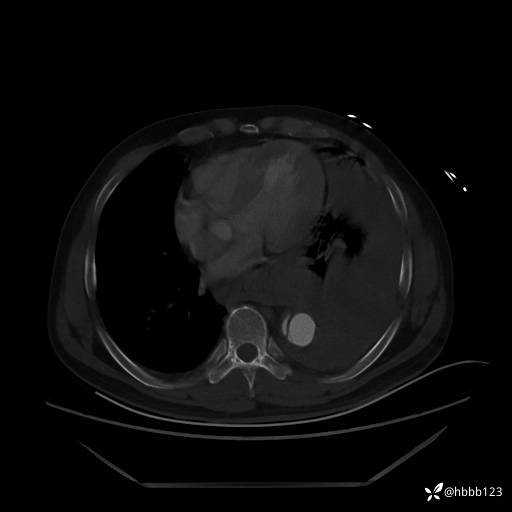

急查胸腹主动脉CTA:

(为方便观察,调至骨窗)